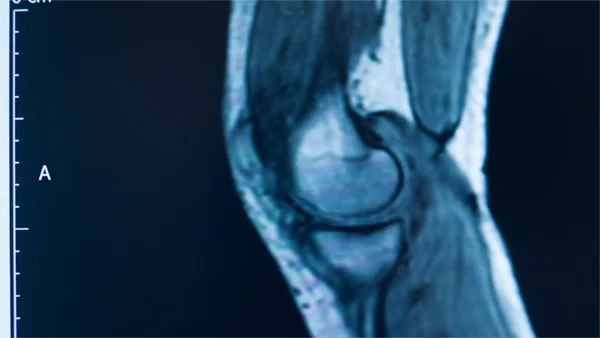

Dr. Khoo provides a comprehensive range of treatments to address various knee conditions, from non-operative therapies to advanced surgical options. Each treatment plan is personalised based on your specific condition, severity, and lifestyle goals. Whether you’re dealing with arthritis, ligament injuries, or cartilage damage, Dr. Khoo is here to help you find the best path to recovery and regain your mobility and quality of life.